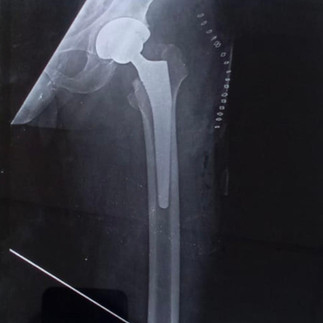

On evaluation, he was diagnosed with advanced osteoarthritis of the hip—a condition caused by wear and tear of the joint due to age and years of physical activity. In such advanced stages, conservative treatments no longer provide relief, and Total Hip Replacement (THR) remains the best option to restore mobility and eliminate pain.

Mr. Kumar courageously opted for surgery. Post-operatively, his recovery was remarkable—he was able to walk the very next day, pain-free and with a smile. For someone who had been living with constant pain, this was nothing short of life-changing.